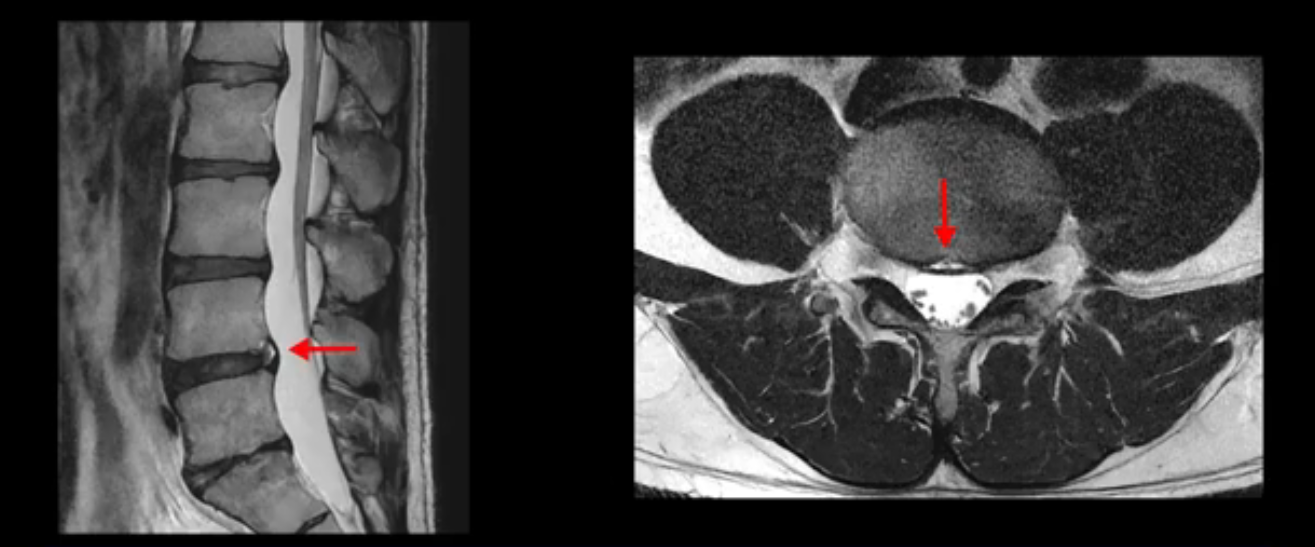

우선 이분 MRI를 보면 허리 모든 마디의 디스크가 퇴행되어 있고

여러 마디의 디스크가 조금씩 밀려나와 보이고, 디스크 섬유륜도 찢어져 보이는 마디도 보입니다.

그런데 이분의 증상과 MRI가 전혀 일치하지 않는데, 왜 그런지 지금부터 자세히 설명드립니다. 이분 증상은 앉으면 엉치와 허리가 심하게 아파 10분 이상 앉는 게 어렵고 양쪽 발가락이 앉아있을 때나 누워있을 때 다 저립니다. 걸을 때도 아파서 10분 걷기도 어렵습니다. MRI를 마디마디 살펴보면 1번 2번은 오른쪽으로 살짝 밀려나온 디스크가 있지만 전혀 심하지 않고, 뒤에 또 설명하겠지만 최근에 밀려나온 급성 디스크가 아니고 오래된 디스크로 판단됩니다.

2번 3번도 비교적 디스크 상태는 좋고 신경 구멍 넓이도 아주 넓습니다.

3번 4번도 마찬가지로 디스크상태 좋아 보이고 신경 눌림 전혀 없어 보입니다.

4번 5번은 가운데로 섬유륜이 찢어져서 디스크가 살짝 밀려나와 있지만 역시나 최근에 찢어지고 밀려나온 걸로 판단되지 않고 오래 전에 찢어진 흔적으로 보입니다.

왜 최근에 찢어진 급성이 아니고 오래된 거라고 하는지 이 부분도 뒤에 한꺼번에 설명 드리겠습니다.

5번 1번 역시 가운데로 디스크 조금 밀려 나와있지만 신경 공간 넓이는 아주 넓어서 신경 눌림 있을 거라고 예상이 안됩니다.

추간공도 보시다시피 왼쪽, 오른쪽 전부 다 매우 넓어서 신경이 눌릴만한 부분이 전혀 보이지 않습니다.